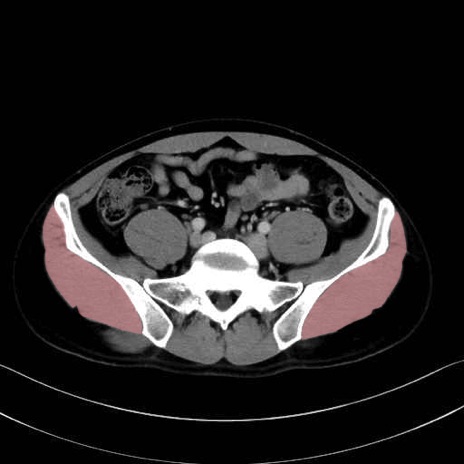

中殿筋 (Gluteus medius)